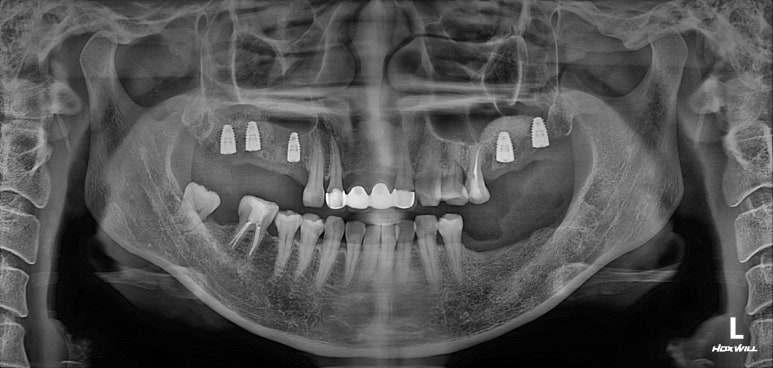

정면에서 보았을 땐, 기존에 제작되어있던 PFM 브릿지가 시간이 지나 그 경계가 조금 보이는 것 말곤 특별히 문제는 없어보였습니다. 아마도 앞니에 큰 문제가 없었기에 내원이 조금 늦어지신 것이 아닌가 싶었어요.

어금니의 상황은 조금 달랐는데요,

오른쪽 위 어금니가 충치와 마모가 심해 뿌리만 남아있는 듯한 모습을 보여주었고,

왼쪽 아래 어금니는 발치되어있는 상황이었습니다.

그리고 무엇보다, 전체 임플란트를 함에 있어 가장 고려대상이 되는 '교합평면'에 어긋나도록 자기 치아를 이탈한 치아들이 많았습니다.

대부분의 수술은 위턱부터 시작합니다.

상악동 뼈이식술을 하면서 임플란트 수술을 시행하였습니다.

왼쪽 위 어금니에 2개, 오른쪽 위 어금니에 3개 총 다섯개의 스트라우만 임플란트를 사용하였습니다.

제 포스팅을 많이 보신 분들은 아실텐데, 상악동 뼈이식술도 함께 진행하였습니다.

내원했을 당시 처음과 비교해보면, 노란선으로 표시된 상악동 뼈이식술 라인을 관찰하실 수 있을겁니다.

상당히 깔끔하게 수술이 이뤄졌네요!

그리고 저희 치과는 치과보존과 전문의 원장님이 함께 계신데, 주황색으로 표시된 두 치아가 깔끔하게 신경치료가 마무리 된 것을 보실 수 있습니다.

깔끔하게 신경치료가 마무리 되면, 보다 조화로운 '교합평면'을 만들어낼 수 있죠.